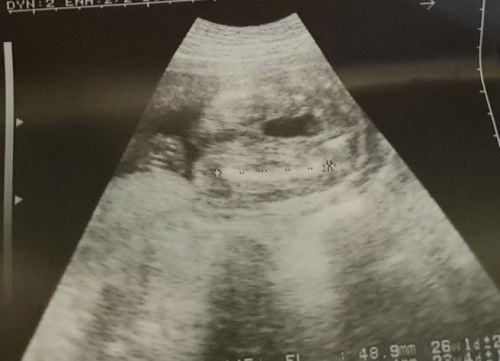

ano po kayang gender ni baby 24 weeks 4days dipo kasi chinagang hanapin ng ob kasi suhi daw po ako at any tips po kung paano umikot si bby ty#1stimemom #advicepls

Girl??? Not sure hehe. Baka makahelp. Breech position https://ph.theasianparent.com/suhi-na-baby https://ph.theasianparent.com/suhi-si-baby

thankyouuuuu sabi po kasi ng ob nung una boy daw po pero baka daw po pusod lang nakita nyaa